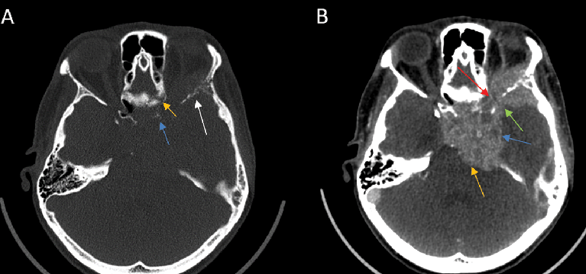

2) Enlargement and/or Erosion of Neural Foramina or Canals (Figs. 2–3). Perineural Spread (PNS) can manifest radiologically as morphological alterations of neural passageways, characterized by foraminal or canal enlargement secondary to neural expansion. This is a delayed finding, as the normal nerve is smaller than the foramen, and it has ample time to enlarge before bone destruction becomes evident. On imaging studies, this enlargement of foramina typically presents as bilateral asymmetry. However, isolated foraminal enlargement demonstrates limited specificity, as it may represent benign pathological processes or anatomical variants. The presence of concurrent foraminal or canal erosive changes provides stronger radiological evidence for malignant processes, particularly PNS, thereby carrying greater diagnostic significance [29]. Enlargement or erosion of neural foramina or canals is more effectively visualized on CT compared to MRI.

Fig. 2. Contrast-enhanced CT, axial plane. A – Bone window, B – Soft tissue window. A – Erosive changes in the lateral wall of the left orbit, greater wing of the sphenoid bone (the white arrow), sphenoid sinus (the yellow arrow), and destruction of the anterior clinoid process (the blue arrow). B – Tumorous, contrast-enhancing masses extending into the left temporal lobe (the blue arrow), pons (the yellow arrow), and orbit via the optic canal (the red arrow) and superior orbital fissure (the green arrow).